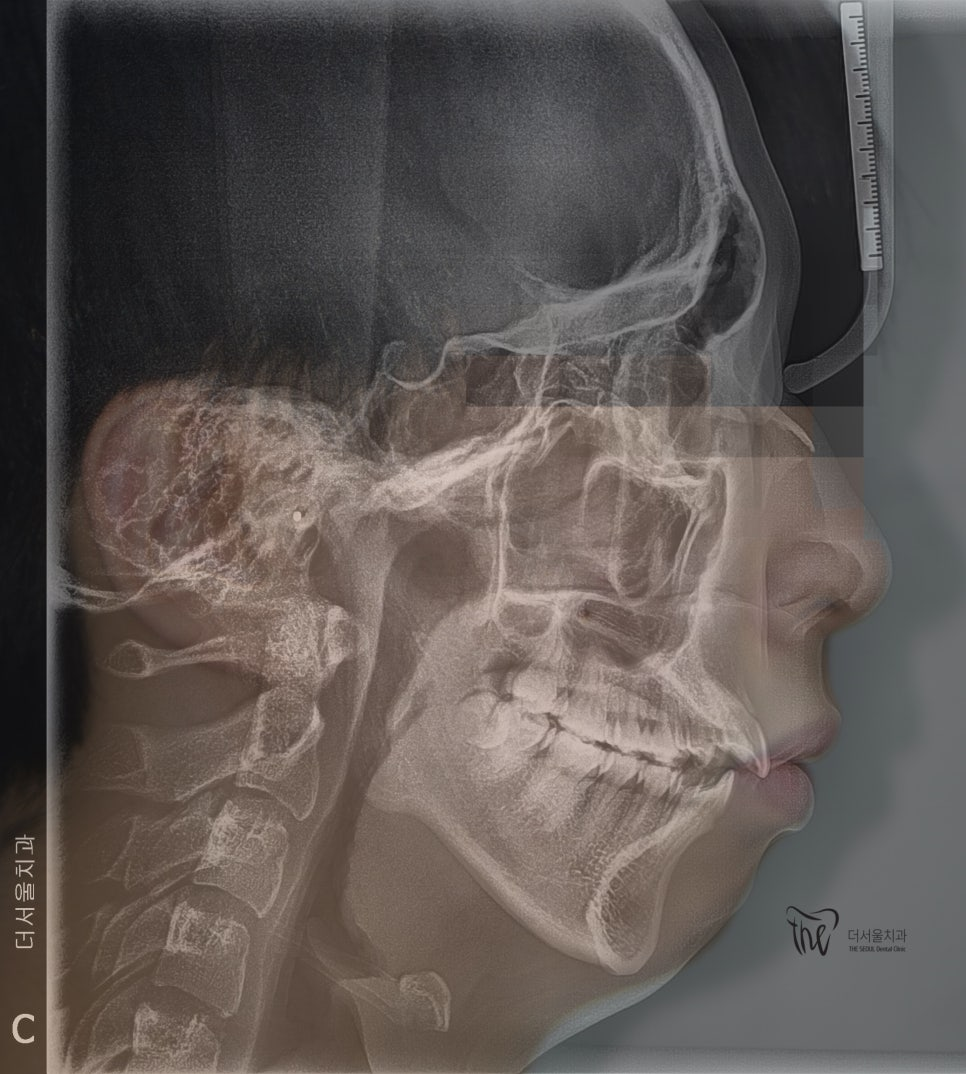

부정교합 2급 이라는 것은, 하악보다 상악이 더 전방에 위치되거나 또는 상악의 치아들이, 하악 치아들보다 더 앞쪽에 위치되어 있는것을 뜻하며

증세를 갖고 계셨던 분의 임상 증례를 보여드립니다. 교정 치료를 통해서 2급 부정교합이 개선 되었으며 치료를 끝으로, 턱 끝에 보형물